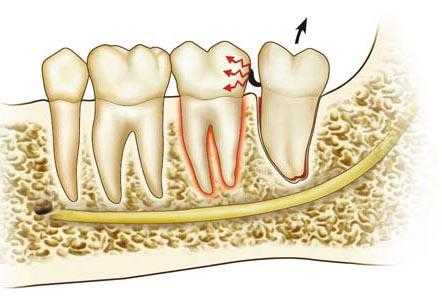

Рис. 63 Вывихивание 2-го моляра при удалении 3-го моляра

Элеватором

Проталкивание корня зуба в мягкие ткани иногда происходит во время удаления третьего нижнего большого коренного зуба. Этому способствует рассасывание в результате патологического процесса тонкой внутренней стенки альвеолы или отламывание ее во время операции. При грубой работе элеватором, когда альвеолярный отросток не фиксируют пальцами левой руки, вывихнутый корень смещается под слизистую оболочку альвеолярного отростка в язычную сторону. При попытке извлечь корень его часто проталкивают еще глубже в ткани подъязычной, реже - поднижнечелюстной области.

Если корень находится под слизистой оболочкой альвеолярного отростка и прощупывается пальцем, то его удаляют после рассечения тканей над ним. Когда удаленный корень обнаружить не удается, делают рентгенограмму нижней челюсти в прямой и боковой проекциях, по которым устанавливают расположение корня в мягких тканях. Корень, сместившийся в ткани заднего отдела подъязычной или поднижечелюстной области, удаляют в условиях стационара.